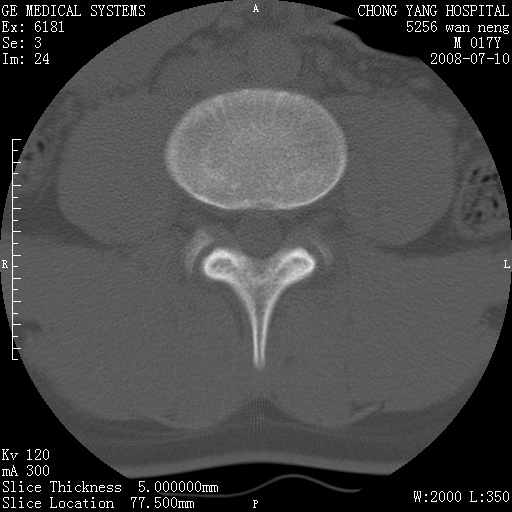

腰3、4椎弓崩裂

腰3、4椎弓不连

支持:腰3、4椎弓峡部崩裂。

腰3、4椎弓峡部不连

支持:腰3、4椎弓峡部崩解。

腰3、4,如受过外伤则为陈旧骨折,否则为骨质不连

图片漂亮,目前也只能看到腰3、4骨质不连

腰3、4椎弓峡部裂。

腰3、4椎弓峡部裂。支持

重建图像见多个椎弓峡部不连(不足为据),平扫未见异常。

支持腰3、4椎弓峡部崩裂。